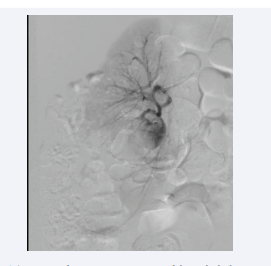

Renal artery DSA was performed which diagnosed a ruptured pseudoaneurysm in the anterior inferior segment artery of the right kidney, measuring 1.6 x 1.3cm in size (Figure 4).

Anterior inferior segment artery of the right kidney.

Figure 4: Anterior inferior segment artery of the right kidney.